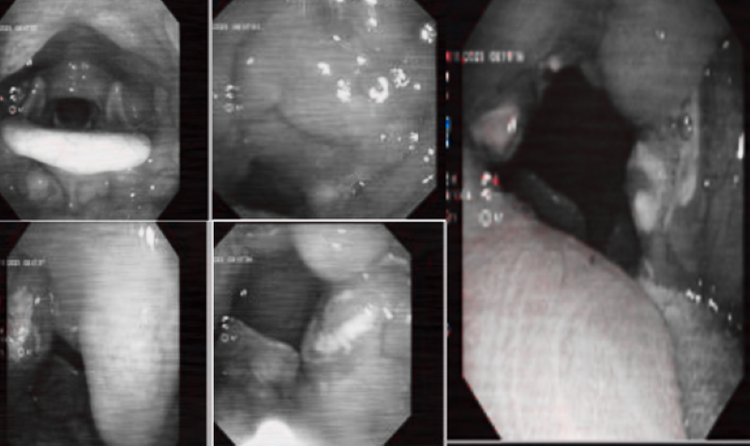

Xét nghiệm nuôi cấy vi khuẩn có vai trò quan trọng trong chẩn đoán viêm amidan cấp mủ/Ảnh Medlatec

Trong chẩn đoán viêm amidan, nuôi cấy vi khuẩn giữ vai trò đặc biệt quan trọng, nhất là trong các trường hợp bệnh tiến triển nặng hoặc không đáp ứng tốt với điều trị ban đầu. Phương pháp này giúp bác sĩ xác định chính xác tác nhân gây bệnh, phân biệt viêm do vi khuẩn hiếu khí hay kỵ khí, từ đó lựa chọn kháng sinh phù hợp và hiệu quả hơn.

Thông qua việc nuôi cấy mủ từ amidan hoặc dịch tỵ hầu, các vi khuẩn gây viêm sẽ được nhận diện cụ thể, hạn chế tình trạng sử dụng kháng sinh không đúng hoặc không cần thiết. Điều này không chỉ giúp nâng cao hiệu quả điều trị mà còn góp phần giảm nguy cơ kháng kháng sinh.

Bên cạnh đó, nuôi cấy vi khuẩn còn có vai trò quan trọng trong chẩn đoán phân biệt. Khi các triệu chứng lâm sàng không điển hình hoặc dễ nhầm lẫn với các bệnh lý tai mũi họng khác, kết quả nuôi cấy giúp bác sĩ xác định chính xác nguyên nhân viêm nhiễm, từ đó đưa ra hướng xử trí kịp thời, hạn chế biến chứng và đảm bảo an toàn cho người bệnh.